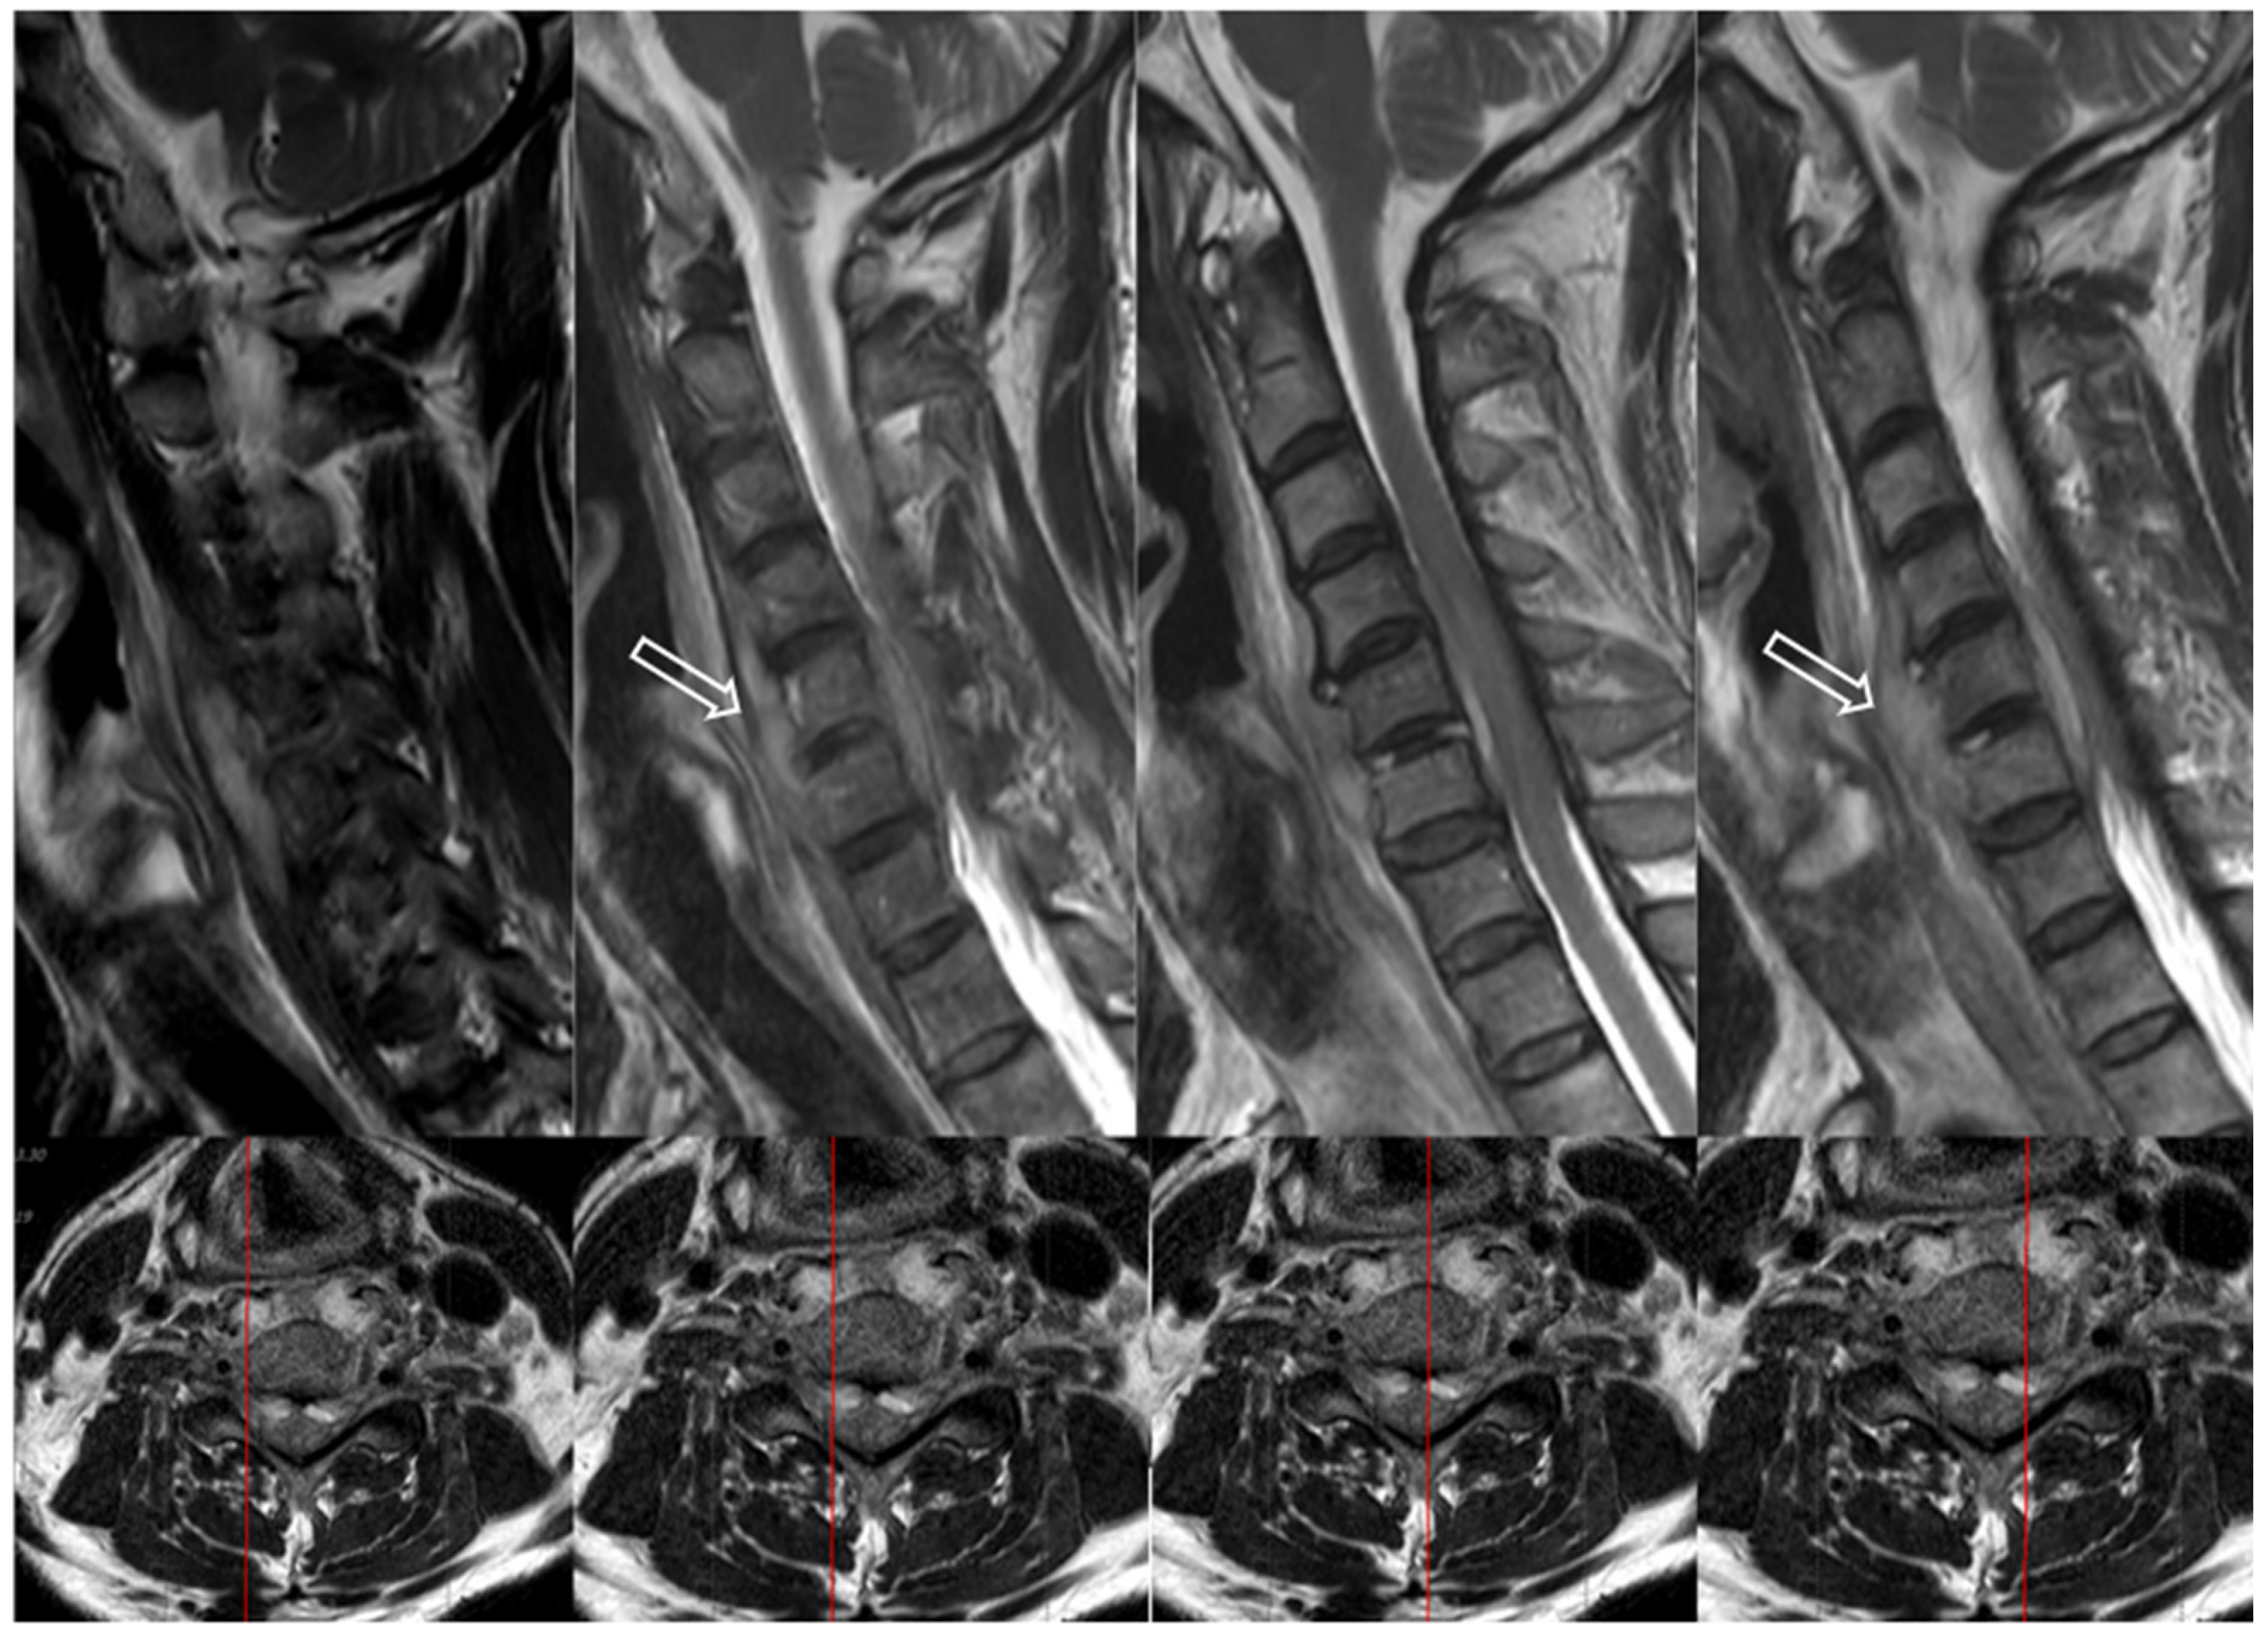

7.3. Imaging Tests